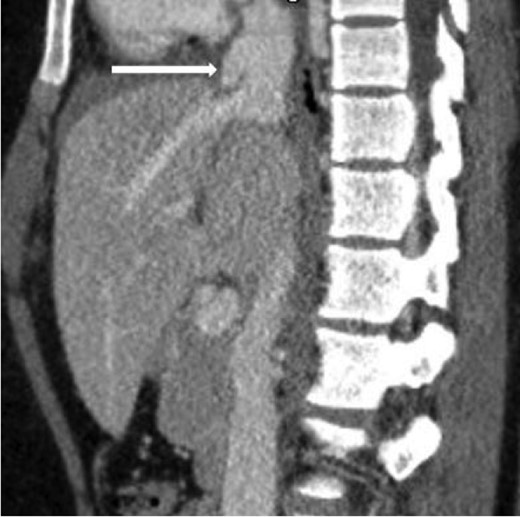

Sagittal contrast-enhanced CT of the abdomen performed 30 min after the initial CT of the chest showing persistence of the abnormal contour of the supradiaphragmatic IVC with contrast extravasation confined laterally and ventrally (arrow), nonexpanding pericaval hematoma.